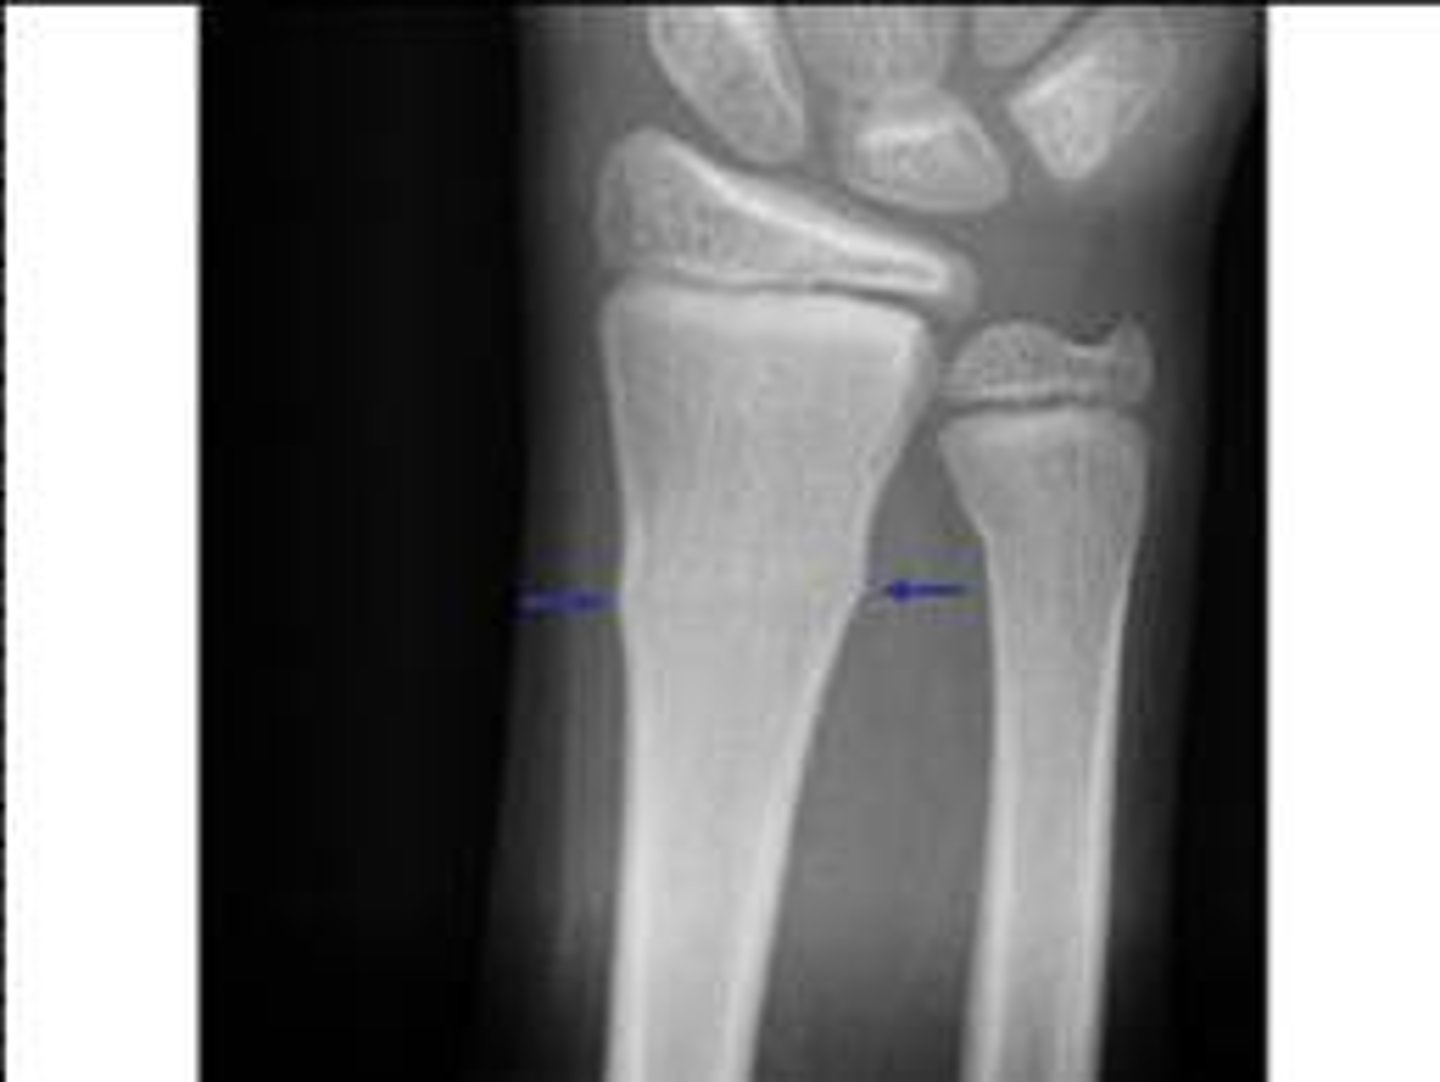

Salter Harris grade 1 growth plate fracture

Salter Harris grade?

Salter Harris grade 2 growth plate fracture

Salter Harris grade 3 growth plate fracture

Salter Harris grade 4 growth plate fracture

Salter Harris grade 5 growth plate fracture

Salter Harris grading scale

a system used to grade pediatric fractures that involve the growth plate (physis), categorized into Types I–V based on the injury's impact on the growth plate, metaphysis, and epiphysis